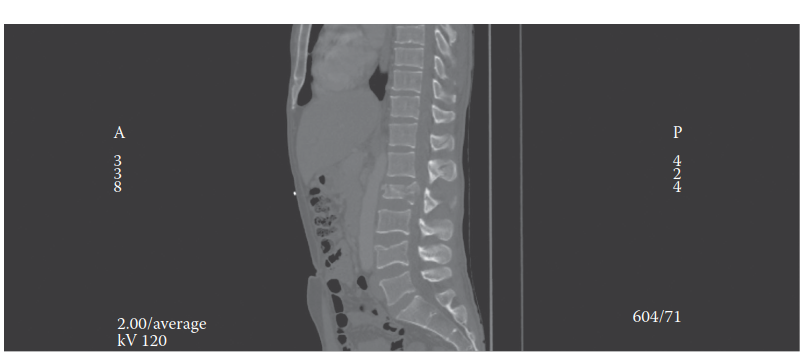

A 32yearold woman is brought to the emergency department following a road traffic collision. She complains of…